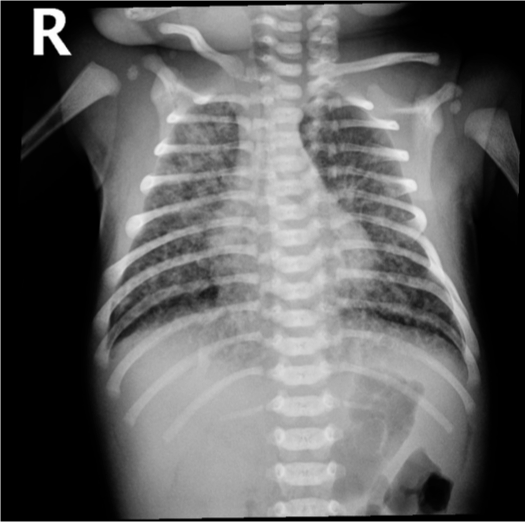

Early BPD changes in Ureaplasma urealyticum pneumonia on day 18 of life

Xray findings

- Hyperinflation,

- Consolidation,

- Patchy infiltrates

- If severe, air leak and pneumomediastinum may occur

- Lines going from inside to outside